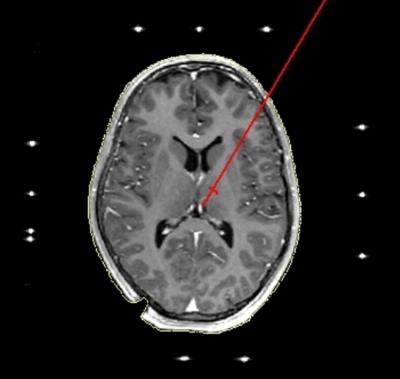

Depressive patients have already been treated with electrostimulation with some success. However, two other areas of the brain were stimulated, located in the forebrain or midbrain regions. The habenula (Latin for the diminutive of reins) is located further downstream next to the brain stem. "We decided to stimulate the habenula because it is involved is the control of three major neurotransmitter systems, which are known to be disturbed in depression,'" explained psychiatrist Dr. Alexander Sartorius from the Central Institute of Mental Health.

The neurosurgical implantation of two electrodes demands utmost precision in planning and performance. The target area is about half as large as the others that are typically targeted for movement disorders, and in addition, is located in the middle of the brain, i.e. in the wall of what is known as the 'third ventricle'. Implanting the electrodes in the two habenulae therefore requires the utmost precision that can currently be achieved with stereotactic instruments. "The neurosurgery department at Heidelberg University Hospital is optimally equipped for demanding procedures such as this with among other things, the new intraoperative highfield MRI," says Dr. Kiening.